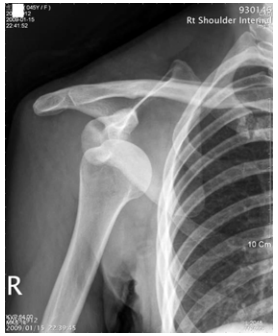

52 45 歲女性,踩在椅凳上擦窗戶時不慎向後跌倒,肩部著地損傷,肩部疼痛、腫脹,呈「方肩」畸形, 彈性固定於肩外展 20~30 度位置,肩關節照 X 光片如圖示,請問診斷為何?

(A)肩關節後脫位 (B)盂下脫位 (C)喙突下脫位 (D)鎖骨下脫位